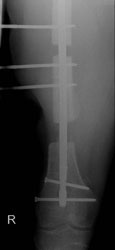

Abbildungen 1 und 2 zeigen einen typischen Defekt der konturgebenden Knochenprojektion im Frontzahnbereich, wie er z. B. – wie hier dargestellt – nach Trauma oder Entzündung entstehen kann (Abb.1 und 2).

Die Rekonstruktion sollte insbesondere in diesem sensiblen Bereich nicht simultan mit der Implantation, sondern präimplantologisch erfolgen. Die Rekonstruktion der sagittalen Projektion im Frontzahn- sowie der transversalen Projektion im Seitenzahnbereich der Juga alveolaria stellt einen hohen Anspruch an die chirurgische Behandlung dar, zumal die Wiederherstellung der gemeinsam mit der Hartgewebsunterlage geschrumpften Weichgewebsdecke bereits vor Behandlungsbeginn berücksichtigt werden muss. Bei Patienten mit hoher Lachlinie, eigentlich aber in jedem Fall der Rekonstruktion des Alveolarfortsatzes, muss die ursprüngliche Projektion nicht nur wiederhergestellt, sondern sogar leicht überdimensioniert gestaltet werden, da das Implantat – gegenüber einer natürlichen Zahn wurzel – von 1 mm – 1,5 mm Knochen allseitig umgeben sein sollte.